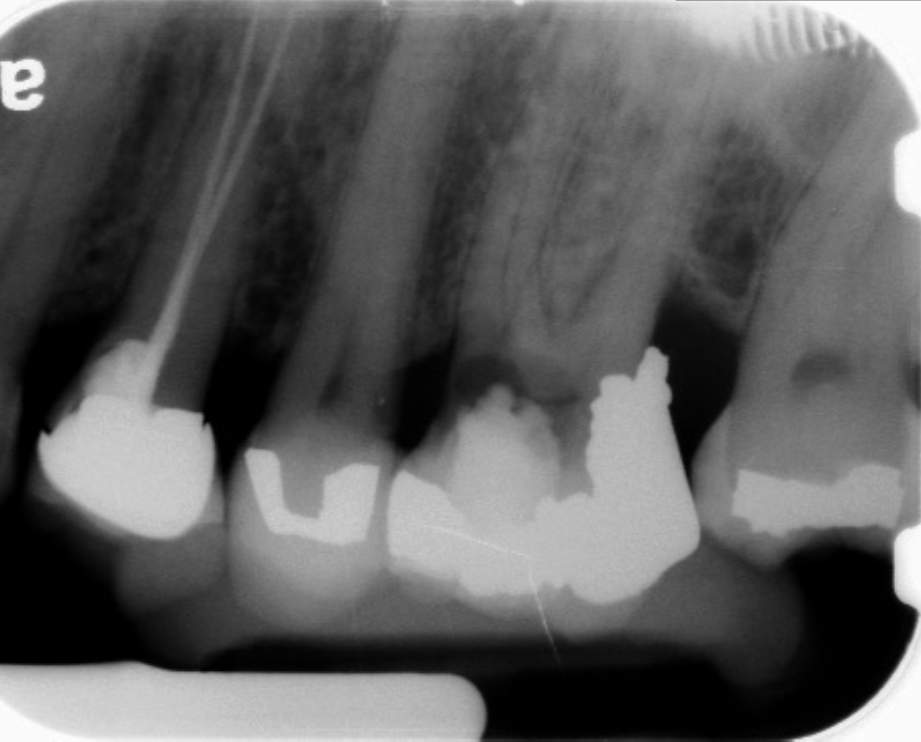

Clinical procedure: If apical bone loss is present (Figure 1) a collagen/gelatin sponge (eg, Gelfoam®, Pfizer Inc., www.pfizer.com) can be placed apically so that the MTA can be delivered to the desired working length. (Any other surgical resorbable sponge would also work, such as OraPlug® [Salvin Dental Specialties, www.salvin.com], Surgifoam® [Midwest Dental, www.mwdental.com], or Surgispon® [Aegis Lifesciences, www.surgispon.com]). This is done by taking a small piece (2 mm x 2 mm) of the resorbable sponge and pushing it down to and through the root apex with an endodontic file. Once this is done, MTA is packed down the canal with a custom-fitted cone. The clinician can use a rubber stopper on the gutta-percha cone to know the exact length of MTA placed in the apical third (Figure 2). Once the apical third is sealed with 3 mm to 5 mm of MTA, the remaining coronal canal space can be back-filled using a warm gutta-percha technique (Figure 3).

Fig 1. Preoperative radiograph showing apical bone loss.

Figure 1

Fig 2. MTA placed in the apical third.

Figure 2

Fig 3. Postoperative radiograph.

Figure 3